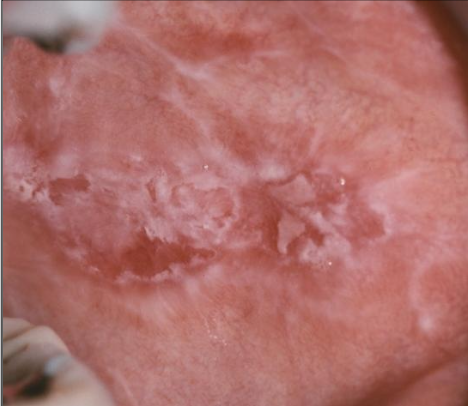

White lace-like striations (Wickham striae), maybe erythematous, bleeding

What is reticular lichen planus?

More common, asymptomatic, lace-like (Wickham striae)

What is erosive lichen planus?

Not as common, painful, erythematous, bleeding